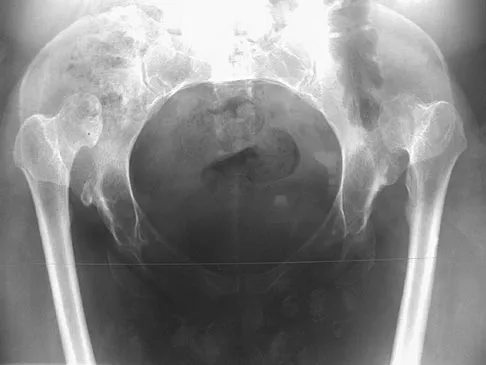

Figures 22a and 22b show the radiographs of a patient who reports stiffness of the hip and associated pain. Management should consist of

The patient has grade IV heterotopic ossification with the limb in an abnormal nonfunctional position. Treatment should consist of excision of the bone to restore hip motion and prophylaxis to prevent recurrent formation. The best time to excise the bone is controversial, with no conclusive evidence supporting early or late excision. Pellegrini VD Jr, Koniski AA, Gastel JA, Rubin P, Evarts CM: Prevention of heterotopic ossification with irradiation after total hip arthroplasty: Radiation therapy with a single dose of eight hundred centigray administered to a limited field. J Bone Joint Surg Am 1992;74:186-200.

- Warren SB, Brooker AF Jr: Excision of heterotopic bone followed by irradiation after total hip arthroplasty. J Bone Joint Surg Am 1992;74:201-210.